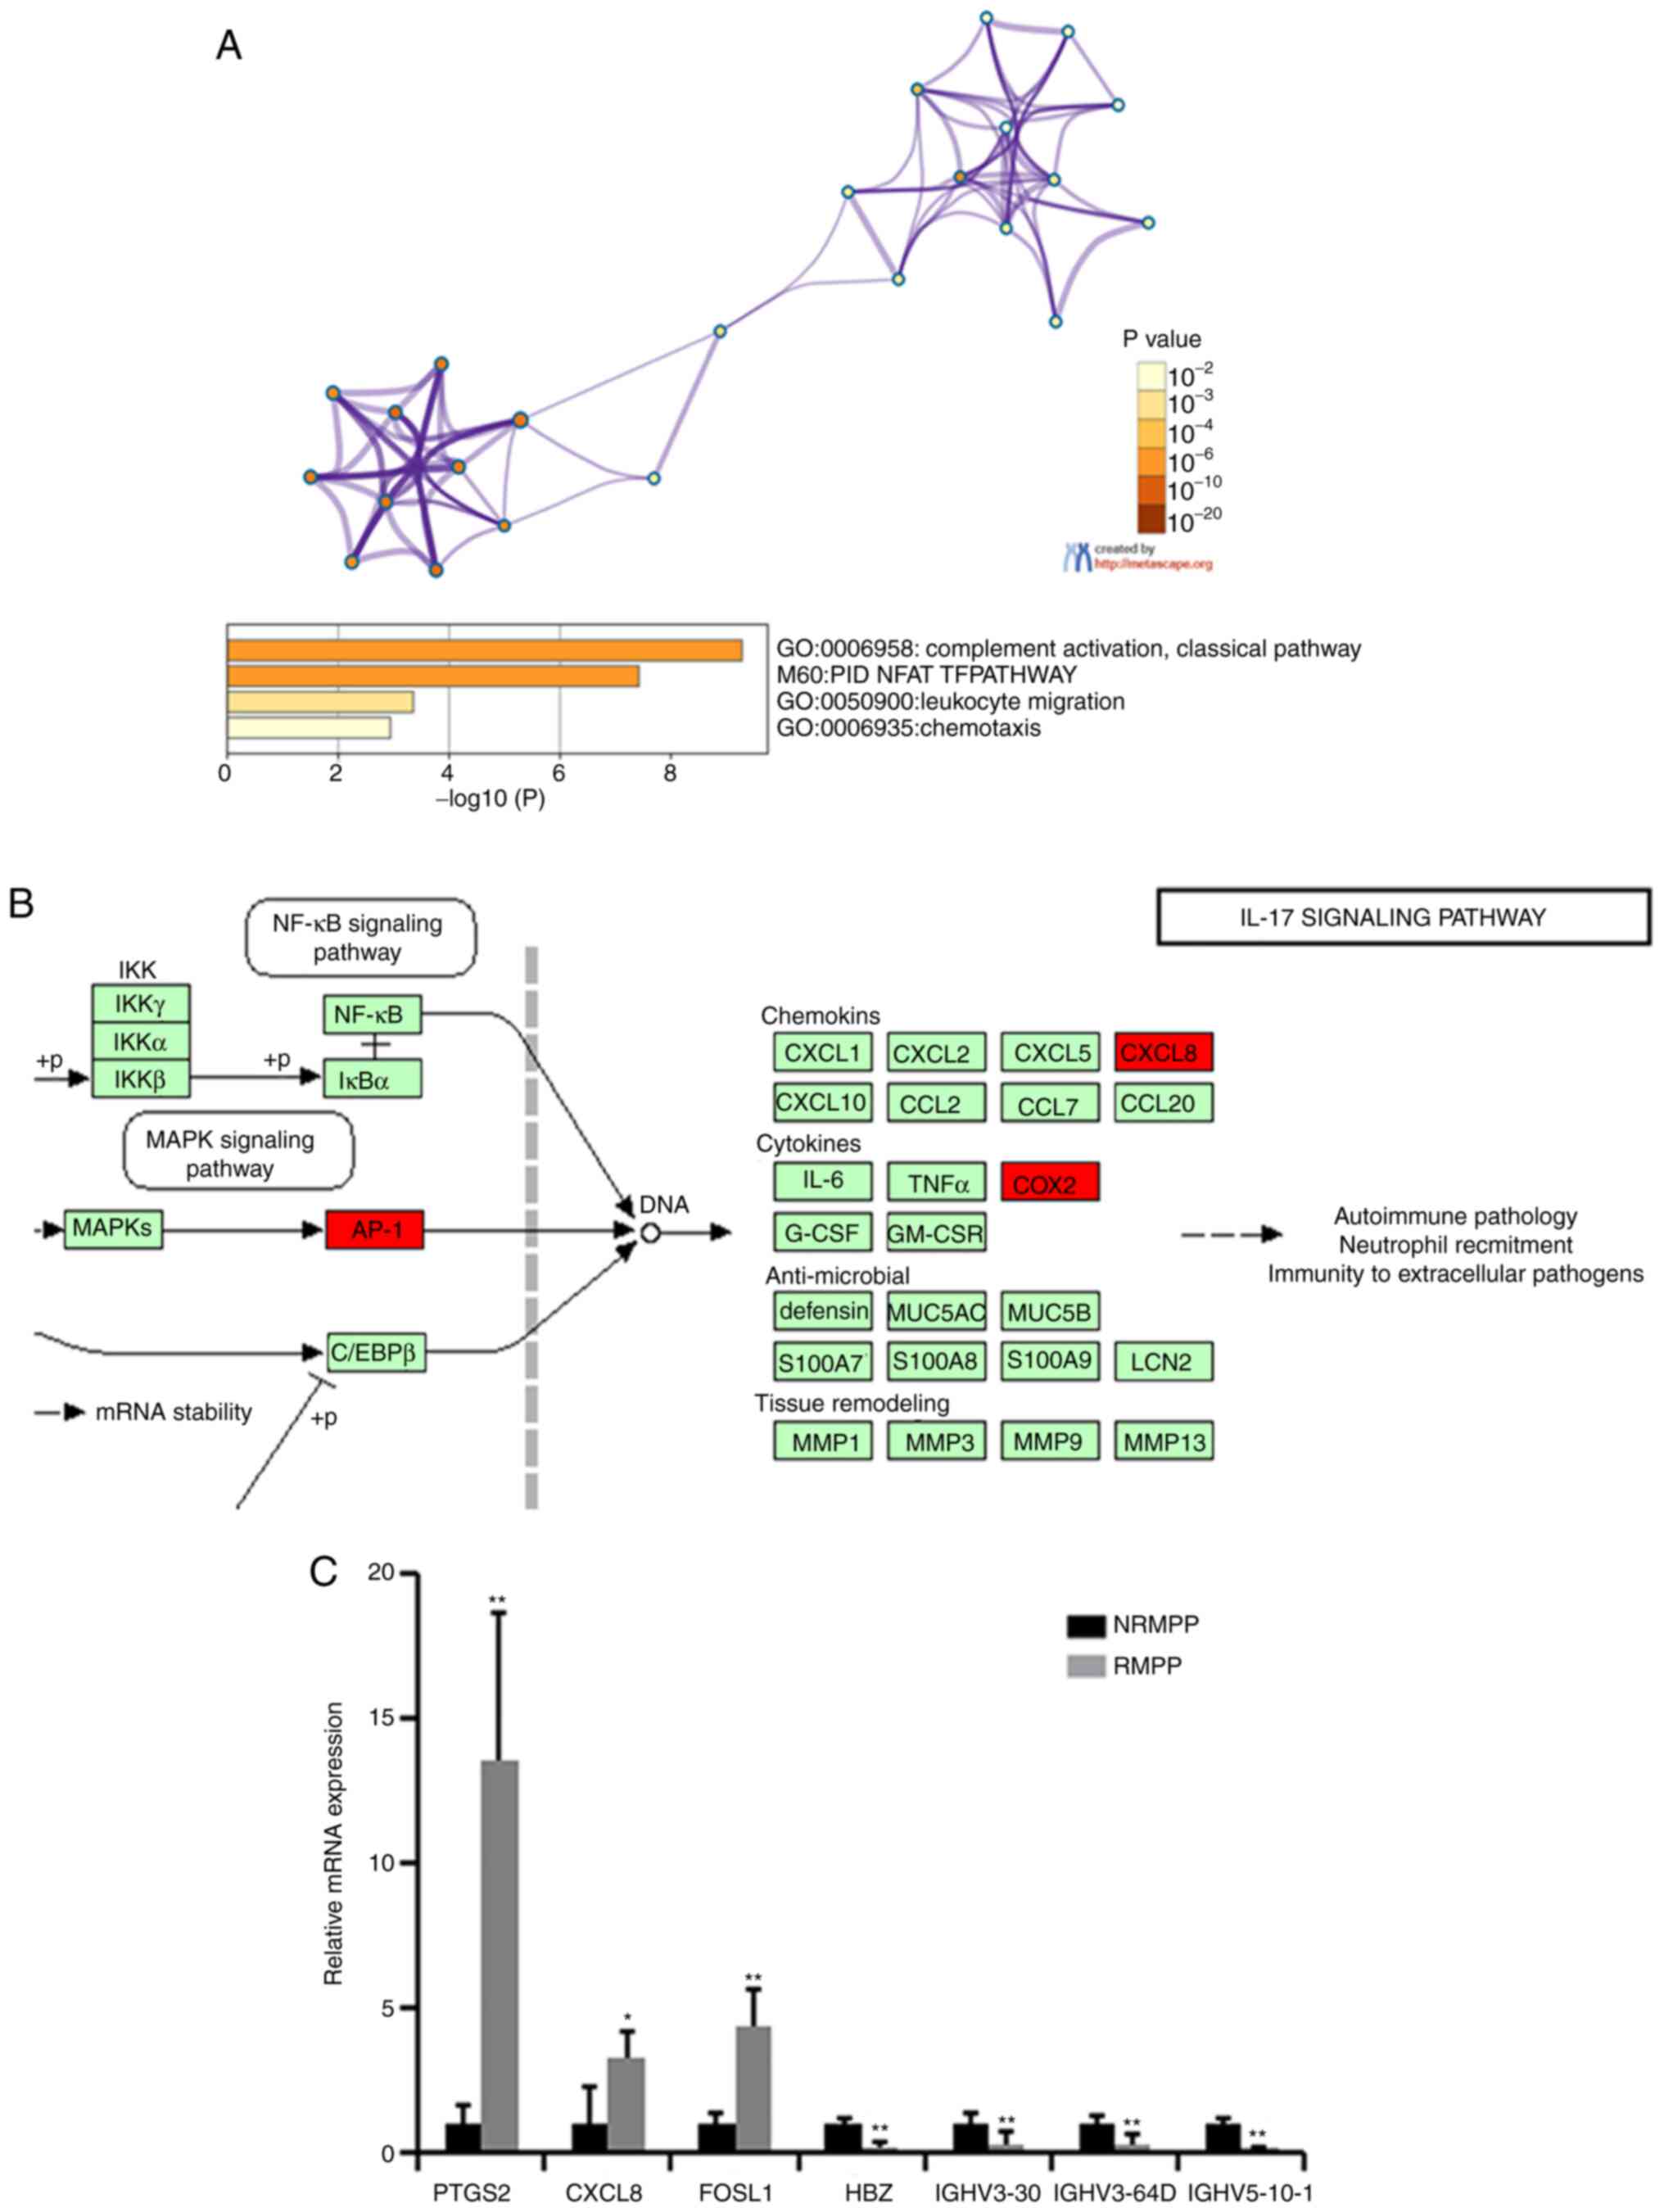

The differentially expressed mRNAs between the RMPP and NRMPP groups (Table IV) were ENSG00000073756, ENSG00000111788, ENSG00000122877, ENSG00000123838, ENSG00000130656, ENSG00000165949; these were identified by functional analysis using both the GO and KEGG databases. In the GO analysis, the significantly differentially expressed mRNAs were primarily enriched in ‘complement activation, classical pathway’, ‘leukocyte migration’ and ‘chemotaxis’ (Fig. 4A). In the KEGG pathway analysis, the significantly differentially expressed mRNAs were primarily enriched in the ‘IL-17 signaling pathway’ (Fig. 4B). RT-qPCR was used to verify candidate genes that may be involved in pathogenesis of RMPP, such as prostaglandin-endoperoxide synthase 2 (PTGS2), chemokine (C-X-C motif) ligand 8 (CXCL8) and Fos-like antigen 1 (FOSL1; Fig. 4C) and the primers were designed by EditSeq software.

circRNAs serve important roles in regulating gene expression by sequestering miRNAs as a sponge at the transcriptional or post-transcriptional levels (16). Thus, circRNAs can regulate a number of processes associated with numerous diseases, such as cancer (16,17). M. pneumoniae possesses a tip-like organelle that permits a highly oriented extracellular parasitism of the respiratory epithelium to avoid clearance by mucosal cilia and phagocytosis, and its adhesion ability is positively correlated with pathogenicity (31). Upregulation of PTGS2 promotes inflammation, which may indicate that more severe inflammation was observed in the RMPP group in the present study (32). IL-8 is a chemotactic factor that attracts neutrophils, basophils and T cells, and it is also involved in neutrophil activation (33). FOSL1 encodes the regulator protein and is involved in cell proliferation, differentiation and transformation (34). The expression of PTGS2, IL-8 and FOSL1 was significantly higher in the RMPP group compared with the NRMPP group in the present study, indicating that the upregulation of these proteins may participate in the pathogenicity of RMPP. In addition, RMPP cases exhibit a high activation level of the IL-17 signaling pathway, which may cause an autoimmune response and disease aggravation (35). Immunoglobulin heavy variable (IGHV)3-30, IGHV3-64D and IGHV5-10-1 belong to the V region of the variable domain of immunoglobulin heavy chains that participate in antigen recognition (36). In the present study, the disappearance of IGHV3-64D and IGHV5-10-1 genes and low expression of the IGHV3-30 gene in the RMPP group may be an important mechanism that leads to RMPP cases due to antigen recognition problems. However, further experiments are required to confirm these hypotheses.